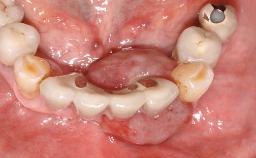

An 83-year-old man presented together with his caregiver at the dental department of the Medical University of Innsbruck, Austria with complaints of swelling in the right maxillary canine area and loss of retention of his 5-years-old mandibular denture. The patient had a significant medical history (20 years) of bipolar affective disorder with moderate depression (F 31.3) and dementia in Alzheimer’s disease (F 00.2). The patient had been in ambulant psychiatric therapy for his depressive illness for the past 20 years. He lived alone and had no children; his sister assisted with daily living. She reported that the patient exhibited compulsive hoarding behavior. In the previous two months, she had noted increasing disorientation and vertigo in the patient. She therefore accompanied him for a medical consultation at the Department of Psychiatry and Psychotherapy of the Medical University of Innsbruck. He was released home after a 6-week inpatient stay.

Case Type Edentulous Mandible

Jaw Mandible

Area Full-Arch

# of Implants 2